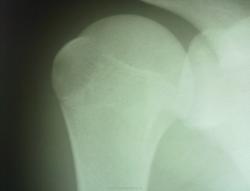

мое мнение- вариант нормы, не закрылись еще зоны роста, если есть сомнения, то можно сделать через несколько дней аксиальную проекцию, когда купируется болевой синдром. Сейчас конечность должна быть мобилизована.

Пока предварительно поставили перелом, завтра аксиальную сделаем с утра, пока флюорограф не включим.Болевой синдром выраженный, рука практически не поднимается, висит плетью.

"рука висит плетью" наводит на мысь о травматическом плексите. Если выраженный болевой синдром, то не нужно спешить, тут же не стоит вопрос об инвазивных методах лечения.

Спасибо за комментарии.Действительно, сегодня с трудом сделали аксиальную-оказалась малоинформативной вследствие недостаточного обезболивания.Пока думаю, что все-таки перелома нет, но посмотрим динамику.Главное, что лечение получает.

Один раз нарвавшись при такой картине на задний вывих плеча всегда стараюсь его исключить. но по этим снимкам очень сложно о чем-то говорить.